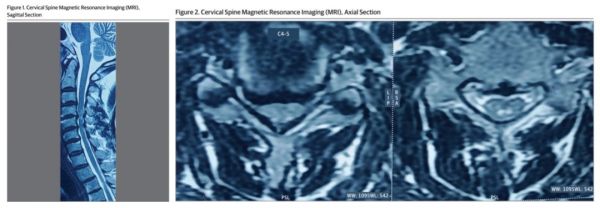

颈椎 MRI(图 1+2)显示:C3-C4 至 C7-T1 水平存在多个椎间盘骨质增生性膨出,导致椎间孔狭窄,且在 C4-C5 水平存在严重的椎管狭窄并压迫脊髓。

根据影像学即可明确病因为:颈椎椎间盘膨出。